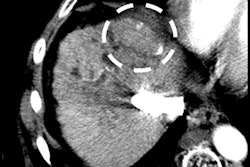

The LI-RADS version 2018 diagnostic algorithm combines imaging features to assign risk categories to liver observations in patients at high risk for hepatocellular carcinoma (HCC), with LI-RADS categories LR-1, LR-2, LR-3, LR-4, and LR-5 corresponding to different levels of risk, the authors explained. Primarily, five major features determine categorization: nonrim arterial phase hyperenhancement (APHE), nonperipheral washout, enhancing capsule, size, and threshold growth.